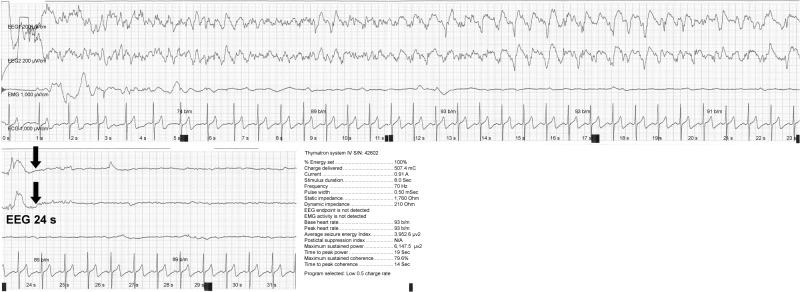

Inducing adequate therapeutic seizures during electroconvulsive therapy (ECT) is sometimes difficult due to a high seizure threshold, even at the maximum stimulus charge. Previous studies have demonstrated that seizure threshold is lower in patients treated with right unilateral ultrabrief pulse (RUL-UBP) ECT than in those treated with bilateral or brief pulse (BL-BP) ECT. Therefore, switching to RUL-UBP ECT may be beneficial for patients in whom seizure induction is difficult with conventional ECT. In the present report, we discuss the case of a patient suffering from catatonic schizophrenia in whom BL-BP ECT failed to induce seizures at the maximum charge. However, RUL-UBP ECT successfully elicited therapeutic seizures and enabled the patient to achieve complete remission. This case illustrates that, along with other augmentation strategies, RUL-UBP ECT represents an alternative for seizure induction in clinical practice.

在电休克治疗(ECT)期间,即使在最大刺激电量下,由于癫痫发作阈值较高,诱导出足够的治疗性癫痫发作有时也很困难。先前的研究表明,接受右侧单侧超短脉冲(RUL-UBP)ECT治疗的患者的癫痫发作阈值低于接受双侧或短脉冲(BL-BP)ECT治疗的患者。因此,对于那些采用传统ECT难以诱导癫痫发作的患者,改用RUL-UBP ECT可能有益。在本报告中,我们讨论了一名患有紧张型精神分裂症的患者的病例,该患者在最大电量下接受BL-BP ECT未能诱导出癫痫发作。然而,RUL-UBP ECT成功诱发了治疗性癫痫发作,并使患者实现了完全缓解。该病例表明,与其他强化策略一起,RUL-UBP ECT是临床实践中诱导癫痫发作的一种替代方法。